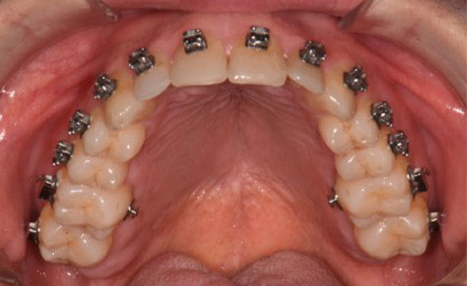

(Images: Intraoral Initial)

From the outset, bracket placement was the cornerstone of the treatment strategy. The upper central incisors were bonded 1–1.5 mm more gingivally than the canines, with laterals slightly lower, to recreate a natural curvature and protect the smile arc. Variable torque brackets were selected individually for each anterior tooth, according to its specific requirements. This feature of the Damon Ultima system represents a significant advantage: it combines the low-friction benefits of self-ligation with earlier expression of anterior torque. When paired with the rapid arch development characteristic of the system, this approach allows for the ideal torque to be achieved very early in treatment. As a result, proclination of the incisors is effectively avoided while maintaining efficient alignment.

The initial alignment was performed with light CuNiTi archwires, promoting gradual expansion and alignment while avoiding heavy forces. Progressively, the treatment advanced to the final 0.018 x 0.0275 stainless steel archwires, ensuring full torque expression and establishing control over the occlusal plane.